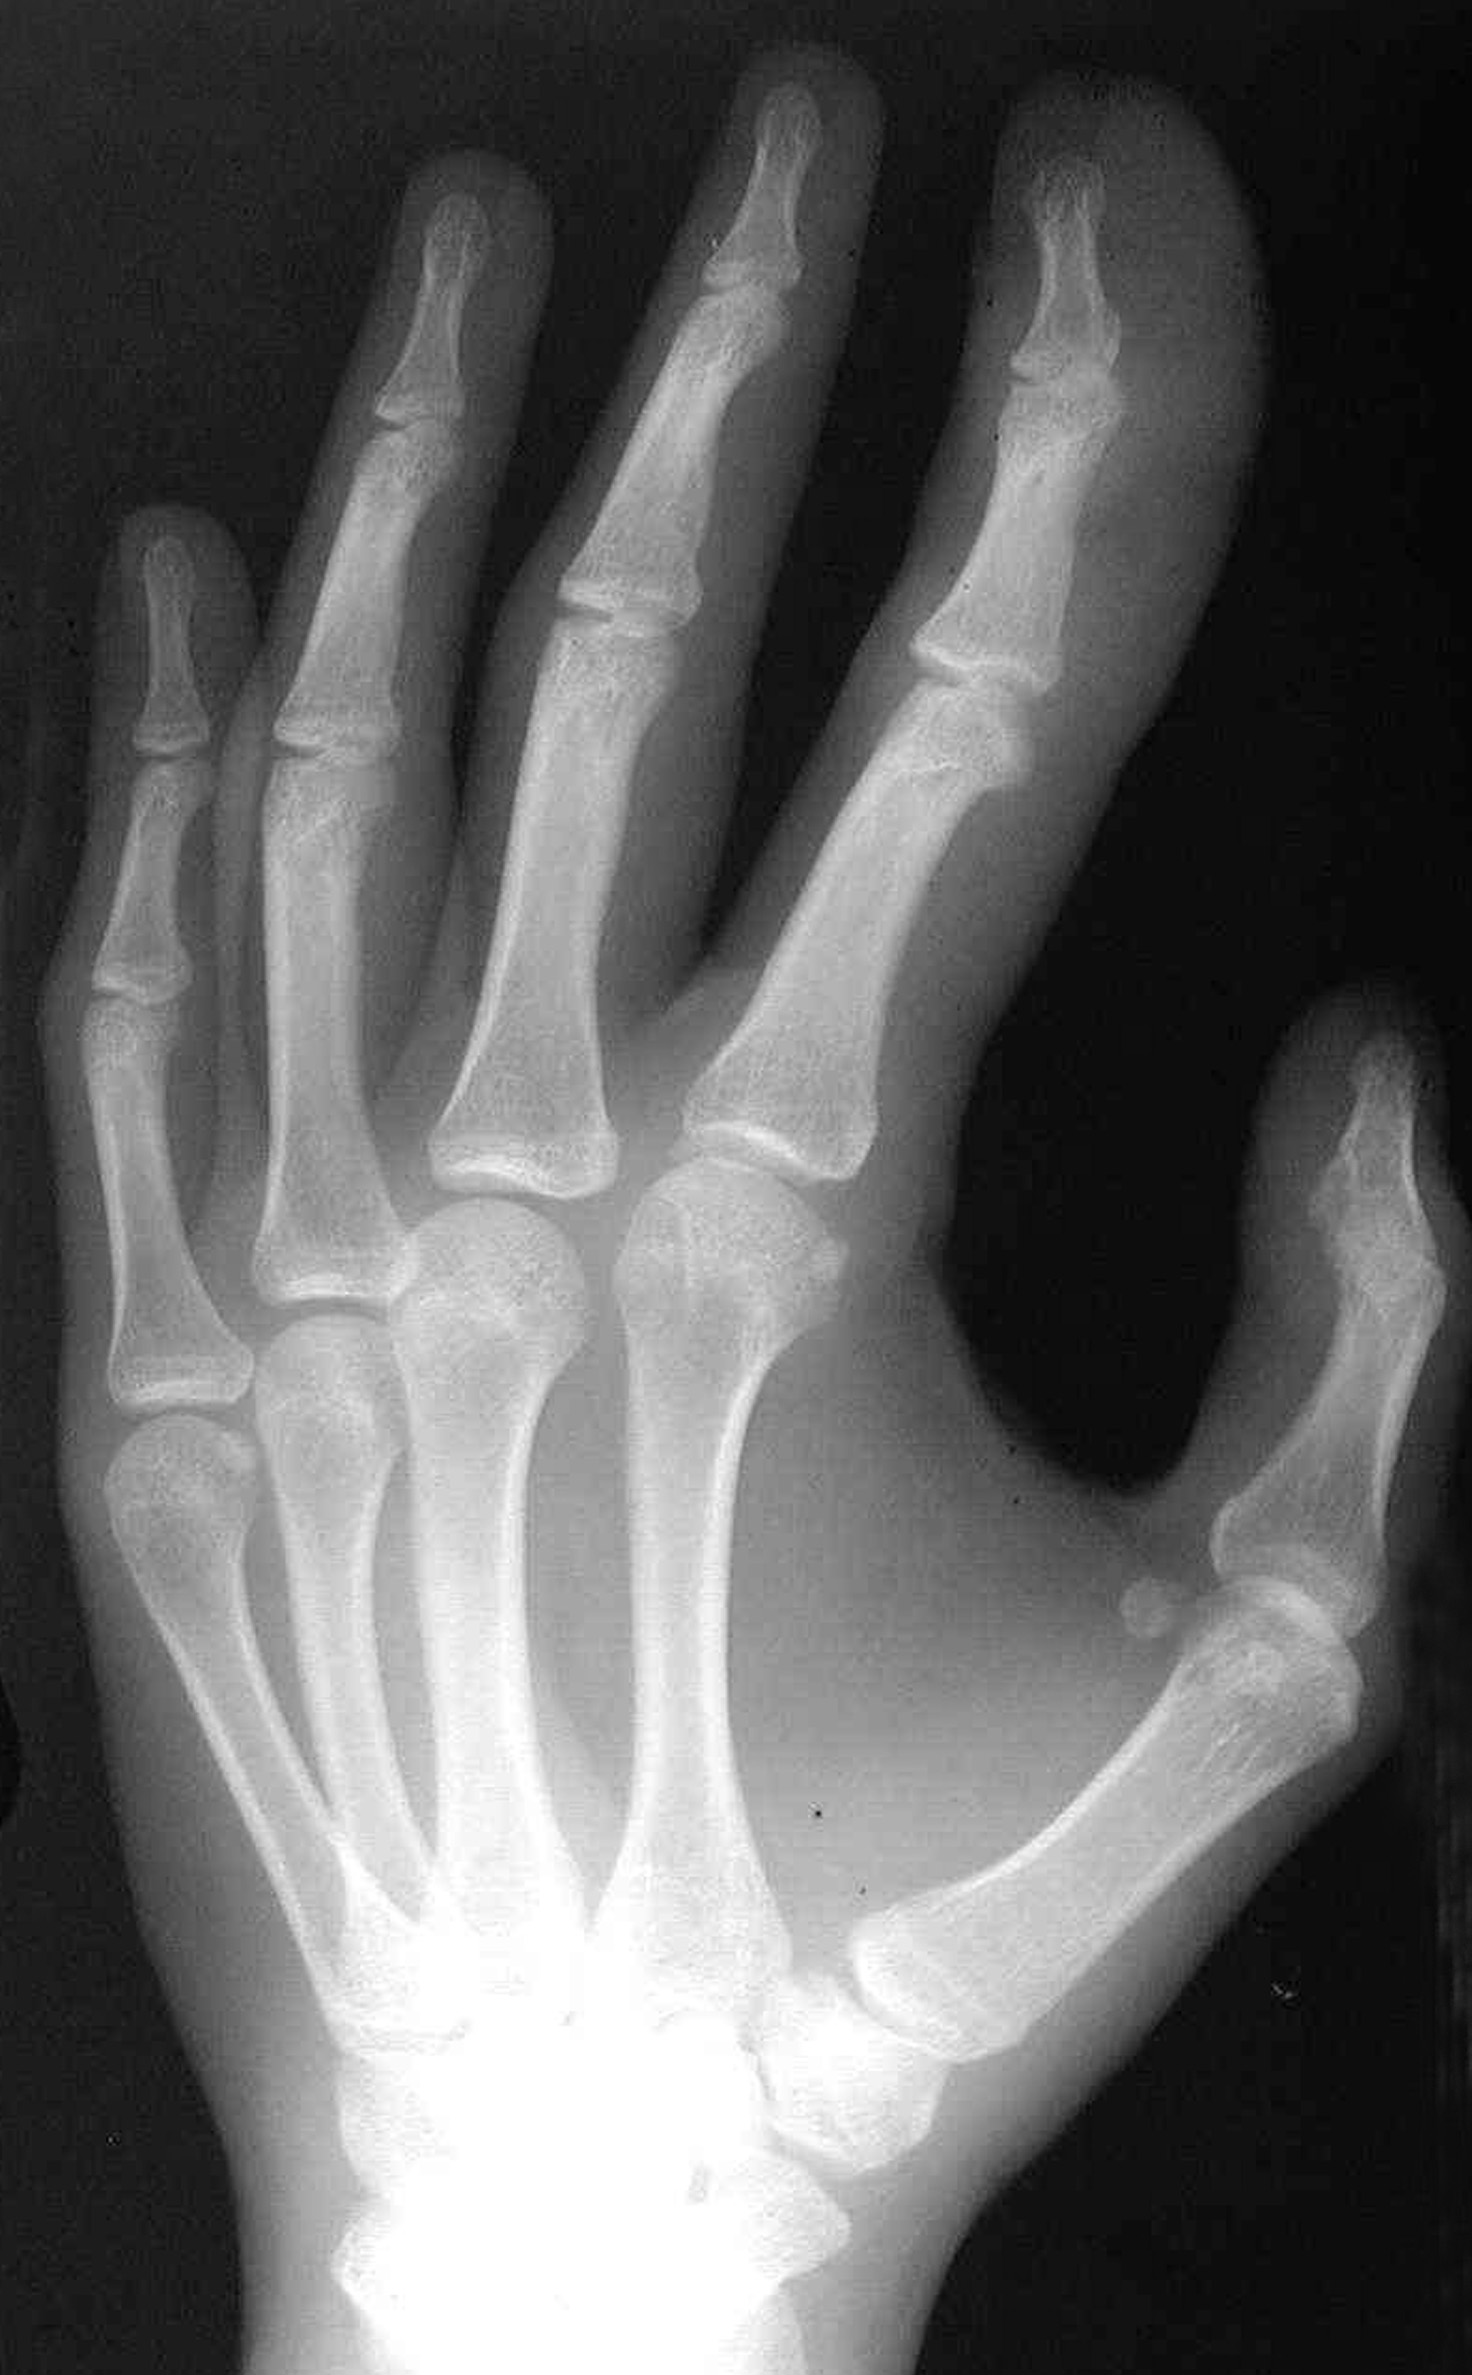

The patient reports no abnormal sensations in the enlarged finger. Significant fatty tissue is present, but there are no discrete masses. He has no pain on palpation or neurologic defect, and the finger has a full range of motion. Oblique and posteroanterior radiographs of the hand are shown.

The radiographs demonstrate prominent soft tissue and bone overgrowth in the finger, consistent with the clinical and radiographic diagnosis of megadactyly. The soft tissue overgrowth is most marked at the distal end of the digit and the volar aspect. The intermetacarpal space is also enlarged. The finger has a slight lateral curve at the apex but no underlying bone deformity. Several lucent areas represent fat. Macrodystrophia lipomatosa was the subsequent diagnosis.